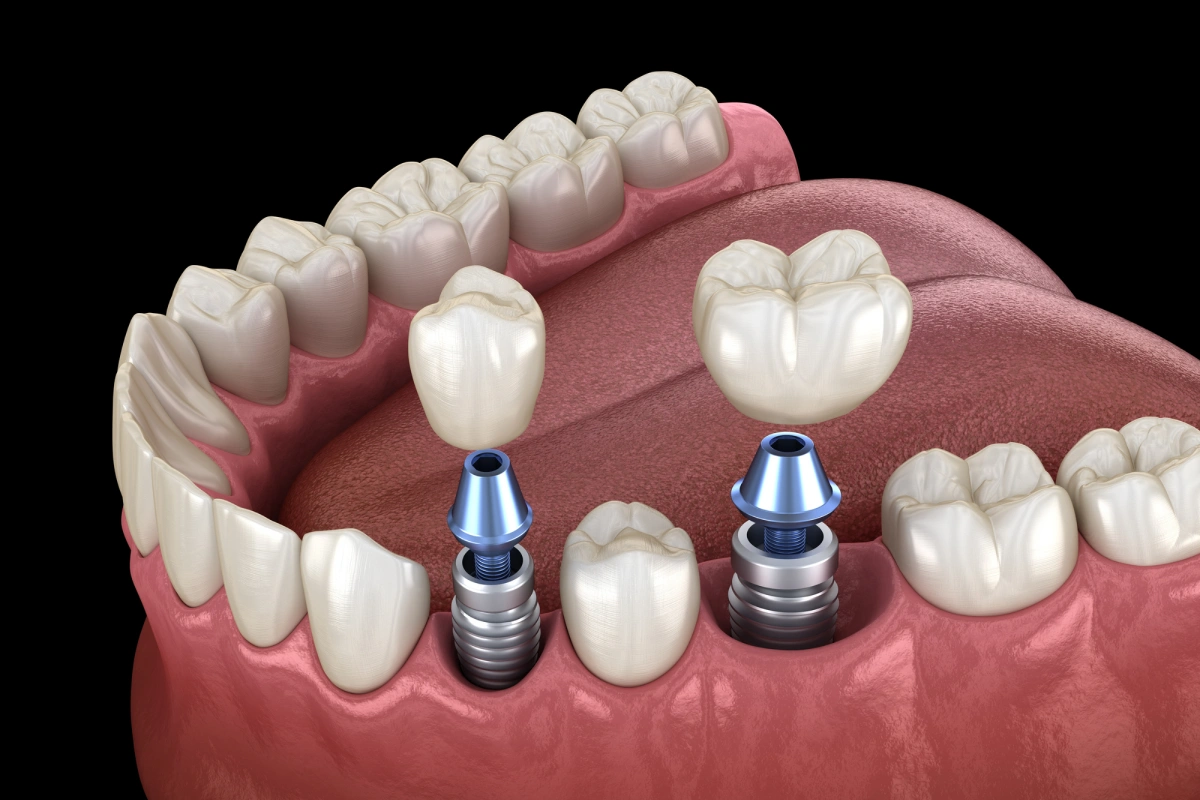

A dental implant is an artificial tooth root, usually made from titanium, that a dentist places directly into the jawbone. Once the implant fuses with the bone through a natural process called osseointegration, a custom crown attaches on top. The result is a replacement tooth that looks, feels, and functions just like the real thing. Unlike removable dentures or a fixed bridge, the implant sits independently in the jaw without relying on surrounding teeth for support. This independence is one of the key reasons so many patients choose implant restorations over other options.

A fixed bridge fills the gap from a missing tooth by anchoring artificial teeth to the natural teeth on each side of the gap. To place a bridge, a dentist must file down and permanently alter those two neighboring teeth, even if they are perfectly healthy, to serve as anchors. The bridge then sits over them like a cap connecting to the artificial tooth in the middle.